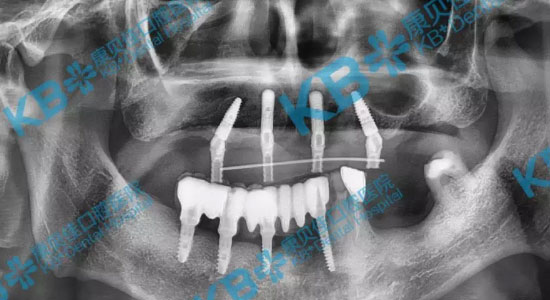

口腔CT拍片后,任势雄博士表示杨叔叔缺牙数量多,缺失的时间也比较久,牙槽骨已经严重萎缩,骨量不足,适合方案是半/全口微创即刻种植。任势雄博士亲自设计了种植方案,将部分坏牙拔除后,上下各植入4颗种植体,为杨叔叔达到了恢复全口牙齿的效果,恢复咀嚼功能。

当天种完牙就能佩戴临时牙冠,牙齿回到了二三十岁的样子和颜色,而且更重要的是当晚就能吃东西了。

“半/全口微创种植牙技术的出现,突破了以往牙槽骨萎缩的种植牙适应症困境。”任势雄博士解释,通过植入4颗/8颗种植体达到重建半口/全口牙齿效果。

老人年纪大,身体耐受力不比年轻人,因此种牙速度必须快——半/全口微创即刻种植牙,利用新鲜的拔牙创口或在牙龈上环切出3-4毫米的切口即可植入种植体,口腔条件好的,一天之内便可种好牙并戴上牙冠。